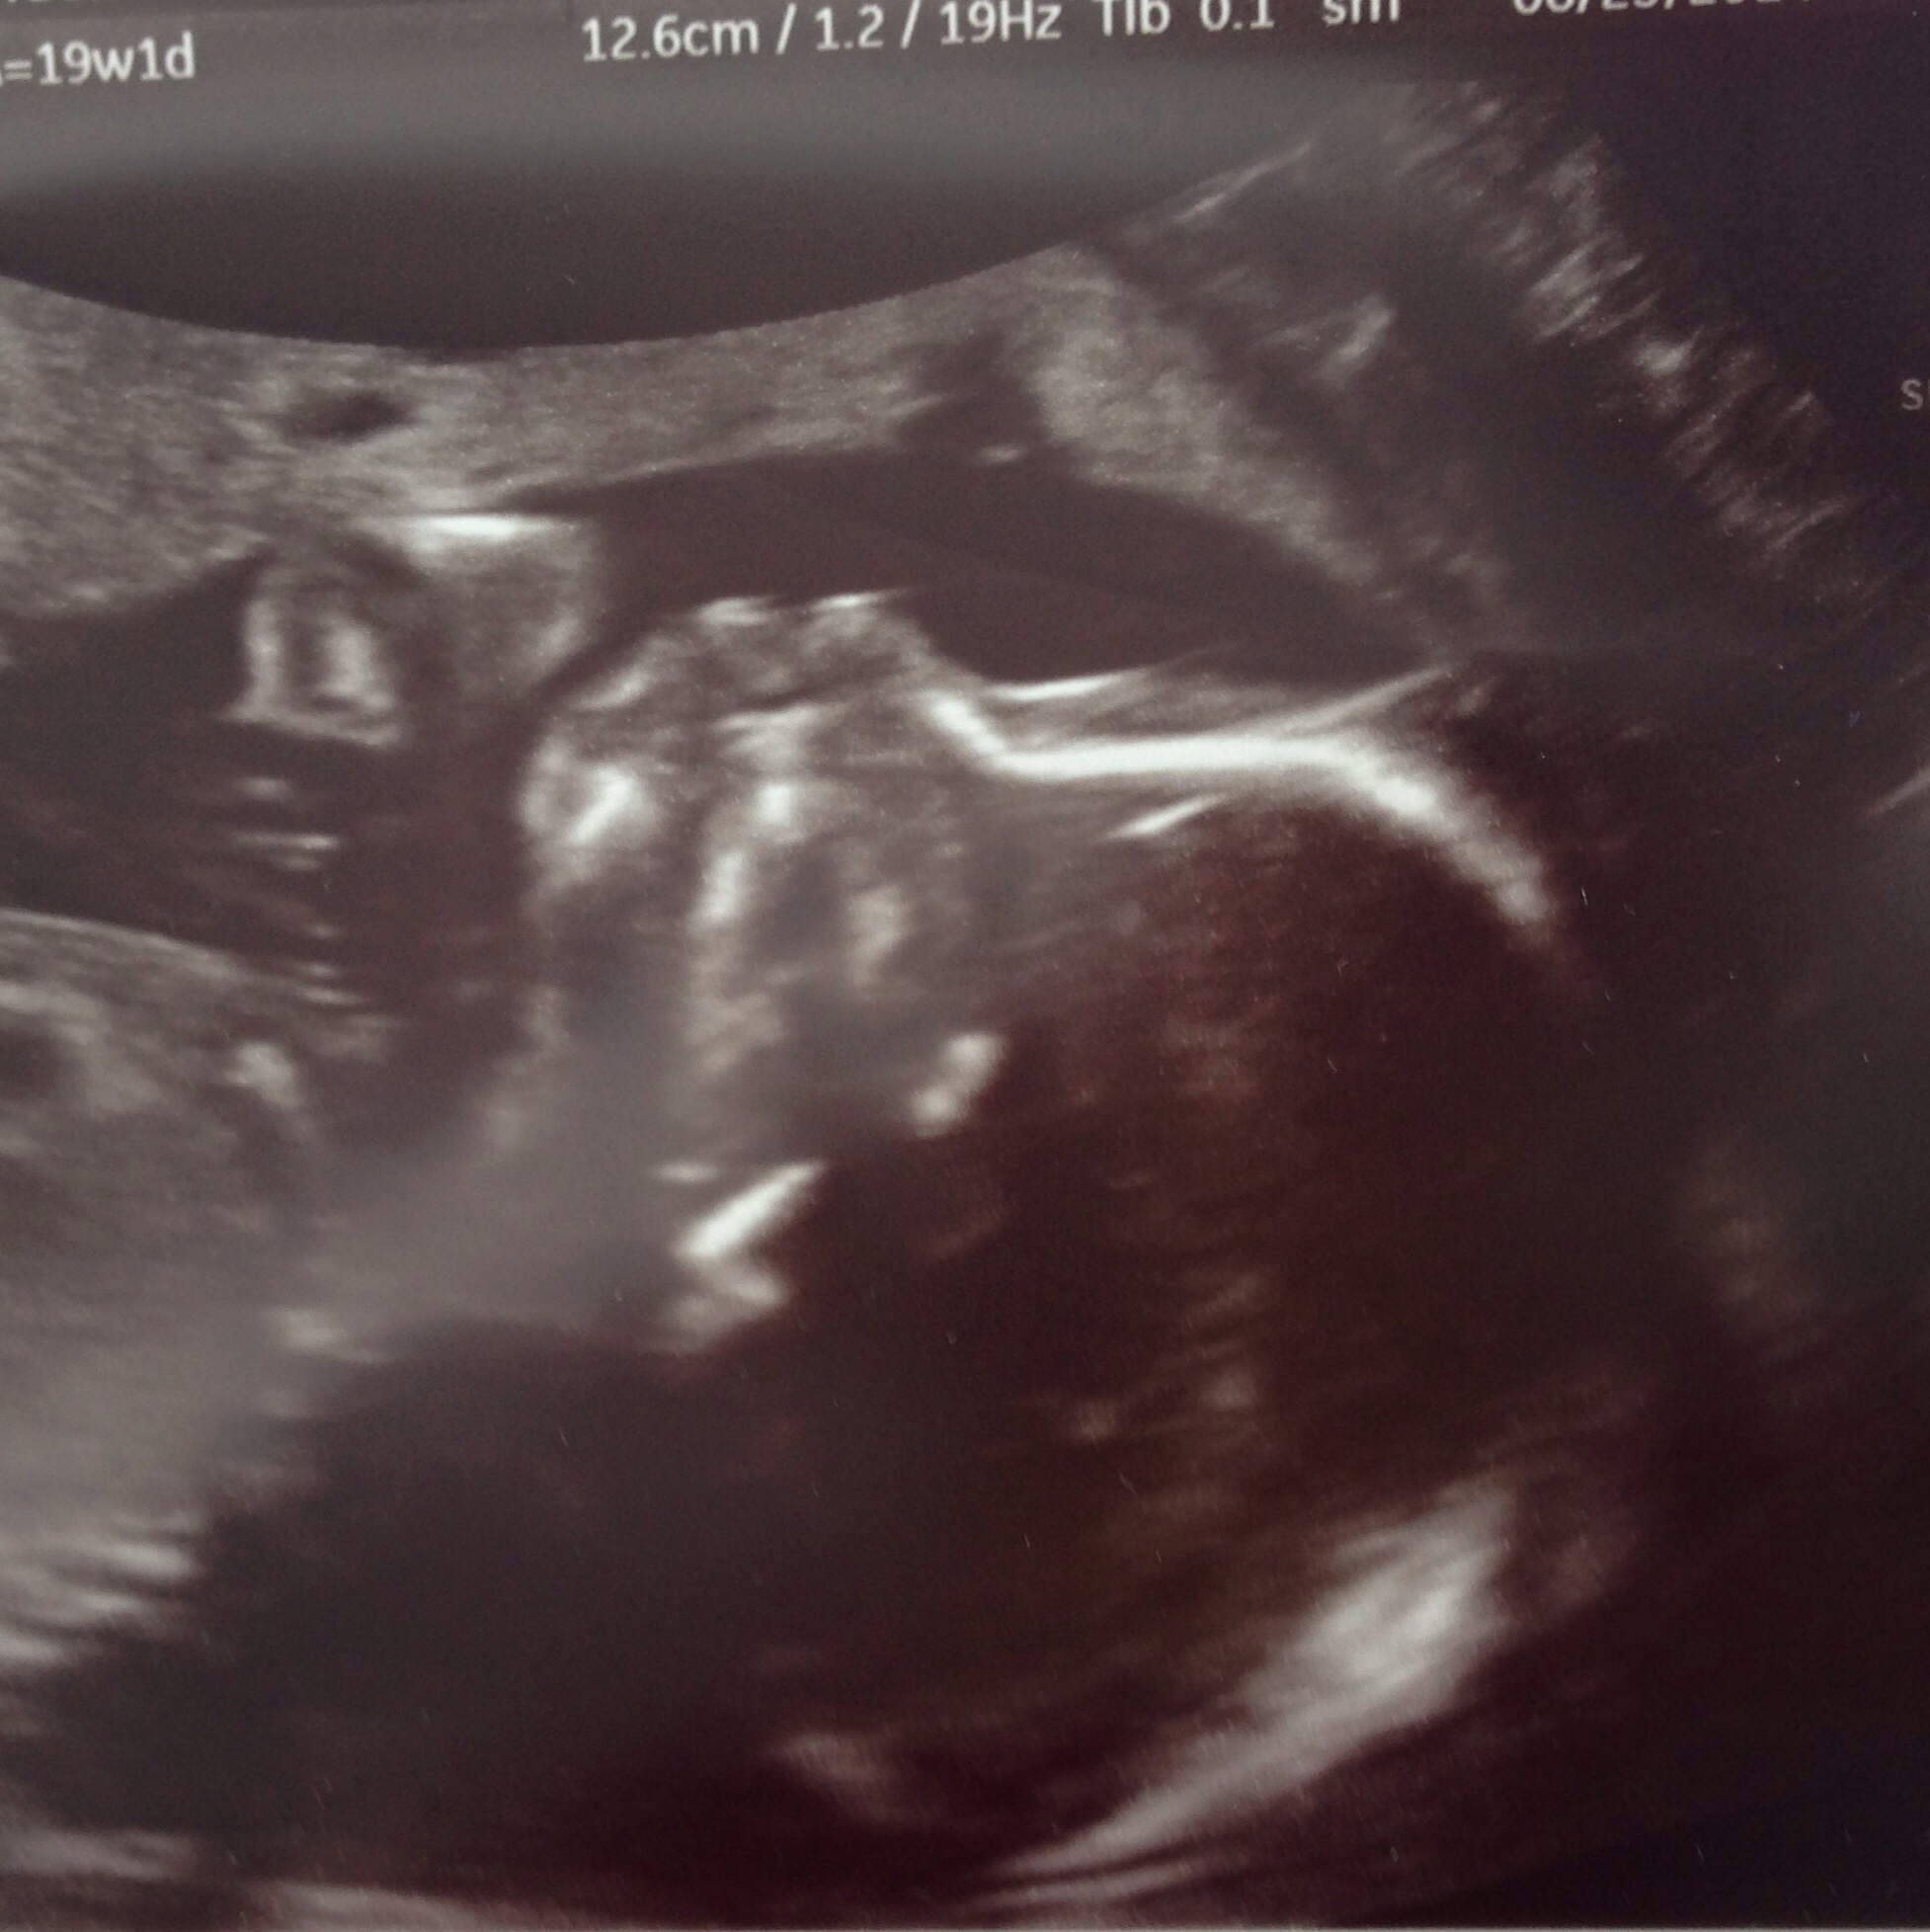

kfo22 said:

Can I join yet???? B-)